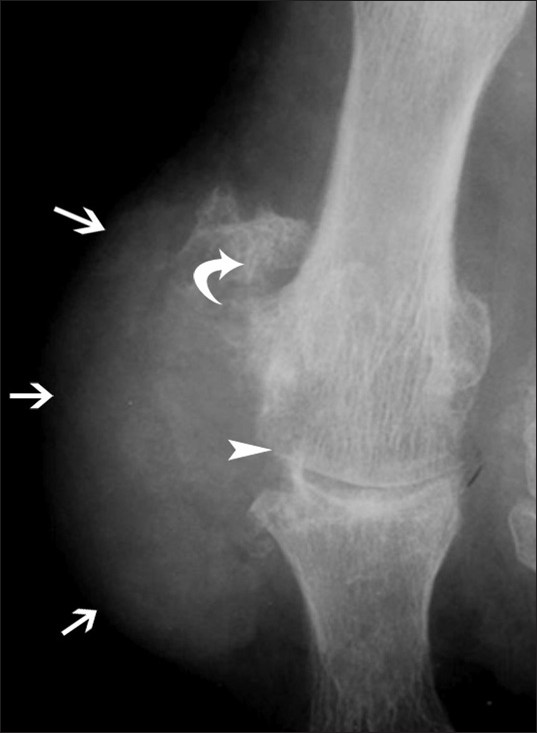

61g3pHBqBoL._AC_UF1000,。Diagnosis of Bone and Joint Disorders (6-Volume Set): Donald。Diagnosis of Bone and Joint Disorders: Resnick, Donald。vマーク おいしい十六穀ごはん 30g×30袋 計900g お徳用。Diagnosis Made Easier: Third Edition: Principles and。Metastatic carcinoma in bone (Chapter 10) - Pathology of。Diagnosis of Bone and Joint Disorders: Resnick, Donald。詳細は写真をご確認ください。Genetic diseases of bones and joints (Chapter 3) - Pathology。。Musculoskeletal Disorders in the Elderly - Journal of。Parameter Selection for Correct Diagnosis on DXA | SpringerLink。。今となっては医学書だと思います。寝付けが難しい本かなと感じております。Bone Disorders: Biology, Diagnosis, Prevention, Therapy。Osteoporosis Treatment Houston TX | Silent Disease League。綺麗な状態だと思います。よろしくお願いします。The Center for Bone & Joint Disease